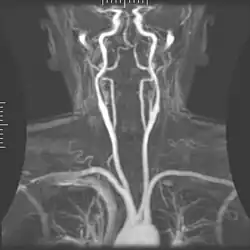

Angiograma de MR em doença cardíaca congênita.

A RM cardíaca é complementar a outras técnicas de imagem, como ecocardiografia, TC cardíaca e medicina nuclear. As suas aplicações incluem avaliação da isquemia miocárdica e viabilidade, cardiomiopatias, miocardite, sobrecarga de ferro, doenças vasculares e cardiopatia congênita.[46]

Angiografia por ressonância magnética

A angiografia por ressonância magnética (MRA) gera imagens das artérias para avaliá-las para estenose (estreitamento anormal) ou aneurismas (dilatação da parede vascular, em risco de ruptura). O MRA é frequentemente usado para avaliar as artérias do pescoço e do cérebro, a aorta torácica e abdominal, as artérias renais e as pernas (chamado de "escorrer"). Uma variedade de técnicas podem ser usadas para gerar as imagens, como a administração de um agente de contraste paramagnético (gadolínio) ou usando uma técnica conhecida como "aprimoramento relacionado ao fluxo" (por exemplo, sequências de tempo de voo 2D e 3D), onde a maior parte do sinal em uma imagem é devido ao sangue que recentemente se mudou para esse plano. As técnicas que envolvem acumulação de fase (conhecida como angiografia por contraste de fase) também podem ser usadas para gerar mapas de velocidade de fluxo com facilidade e precisão. A venografia por ressonância magnética (MRV) é um procedimento similar que é usado para imagens de veias. Neste método, o tecido agora está excitado inferiormente, enquanto o sinal é recolhido no plano imediatamente superior ao plano de excitação - criando assim o sangue venoso que recentemente se moveu do plano excitado.[52]